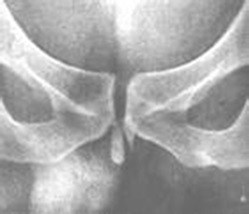

4、肾结石是尿结石最常见的一种,它具有的临床表现有: 1、疼痛:不明显或隐痛;2、血尿:多为镜下血尿;3、尿砂:自行排出小结石 ;4、肾区可有叩痛。